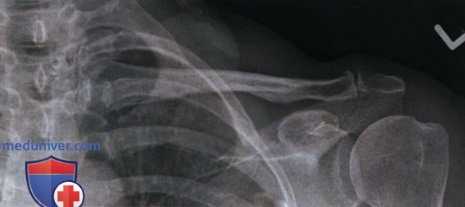

РИСУНОК 1 Рентгенограмма ключицы в аксиальной ПЗ проекции, демонстрирующая ее правильное положение. РИСУНОК A Рентгенограмма ключицы в ПЗ проекции. Пациент повернут в противоположную сторону от исследуемой ключицы. РИСУНОК B Рентгенограмма ключицы в ПЗ проекции. Пациент повернут в сторону исследуемой ключицы.

• Медиальный конец ключицы находится вблизи латерального края позвоночного столба (рис. А и B)

• Верхний угол лопатки визуализируется на 1,25 см ниже ключицы

• Медиальный конец ключицы накладывается на первое, второе и третье ребра

• Средняя и латеральная трети ключицы визуализируются выше акромиального отростка, ключица изогнута вверх (рис. 3 и 4)

• Середина ключицы находится в центре экспозиционного поля

• В экспозиционное поле входят ключица и акромиальный отросток

РИСУНОК 3 Рентгенограмма ключицы в ПЗ проекции: перелом. РИСУНОК 4 Рентгенограмма ключицы в аксиальной ПЗ проекции: перелом.

а) Ротация туловища. Если при рентгенографии ключицы в аксиальной ПЗ проекции туловище повернуто в противоположную сторону от исследуемой ключицы, на рентгенограмме медиальный конец исследуемой ключицы будет накладываться на позвоночный столб (см. рис. А).

Если при рентгенографии ключицы в аксиальной ПЗ проекции туловище повернуто в сторону исследуемой ключицы, на рентгенограмме медиальный конец исследуемой ключицы будет отодвинут от позвоночного столба, а сама ключица подвергнется продольному проекционному укорочению (см. рис. В). И в ПЗ, и в аксиальной ПЗ проекции ротация выглядит схоже, однако на рентгенограмме в аксиальной ПЗ проекции ключица относительно грудной клетки будет визуализироваться выше.

б) Наклон ЦЛ. При рентгенографии ключицы в аксиальной ПЗ проекции краниальный наклон ЦЛ на 15-30° позволяет спроецировать большую часть ключицы выше грудной клетки и оценить степень смещения отломков при наличии перелома. Несмотря на то, что степень наклона в разных медицинских учреждениях может различаться, на всех рентгенограммах ключица будет сдвинута вверх.

Чем больше угол, тем выше будет проецироваться ключица. Поскольку в 80% случаев перелом ключицы происходит в ее средней трети и в 1 5% случаев — в ее латеральной трети, целесообразно ЦЛ наклонять так, чтобы латеральная и средняя трети ключицы визуализировались выше грудной клетки и лопатки. Сравните рентгенограммы на рис 3 и 4 (см. выше) и обратите внимание, как увеличение краниального наклона ЦЛ позволяет спроецировать латеральную и среднюю трети ключицы выше лопатки. На обеих рентгенограммах перелом ключицы очевиден, однако без рентгенограммы в аксиальной ПЗ проекции перелом ключицы без смещения на фоне лопатки можно не заметить.